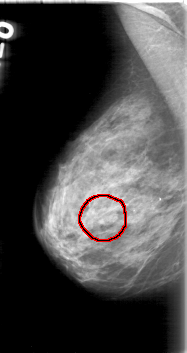

FILE: D_4013_1.RIGHT_CC.OVERLAY

TOTAL_ABNORMALITIES 1

ABNORMALITY 1

LESION_TYPE MASS SHAPE LOBULATED MARGINS OBSCURED

ASSESSMENT 0

SUBTLETY 5

PATHOLOGY BENIGN

TOTAL_OUTLINES 1

BOUNDARY